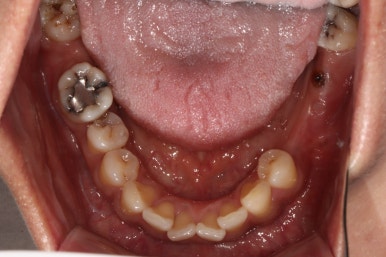

아래턱 교합면입니다.

역시나 충치가 심했던 사랑니는 제거되었고, 비어있던 자리는 임플란트로 대체되었습니다.

색깔과 모양이 상당히 마음에 드는 완성도입니다.

이제 진짜.. 자연치라고 해도 잘 모를 정도로 치과치료의 완성도가 높아졌습니다.